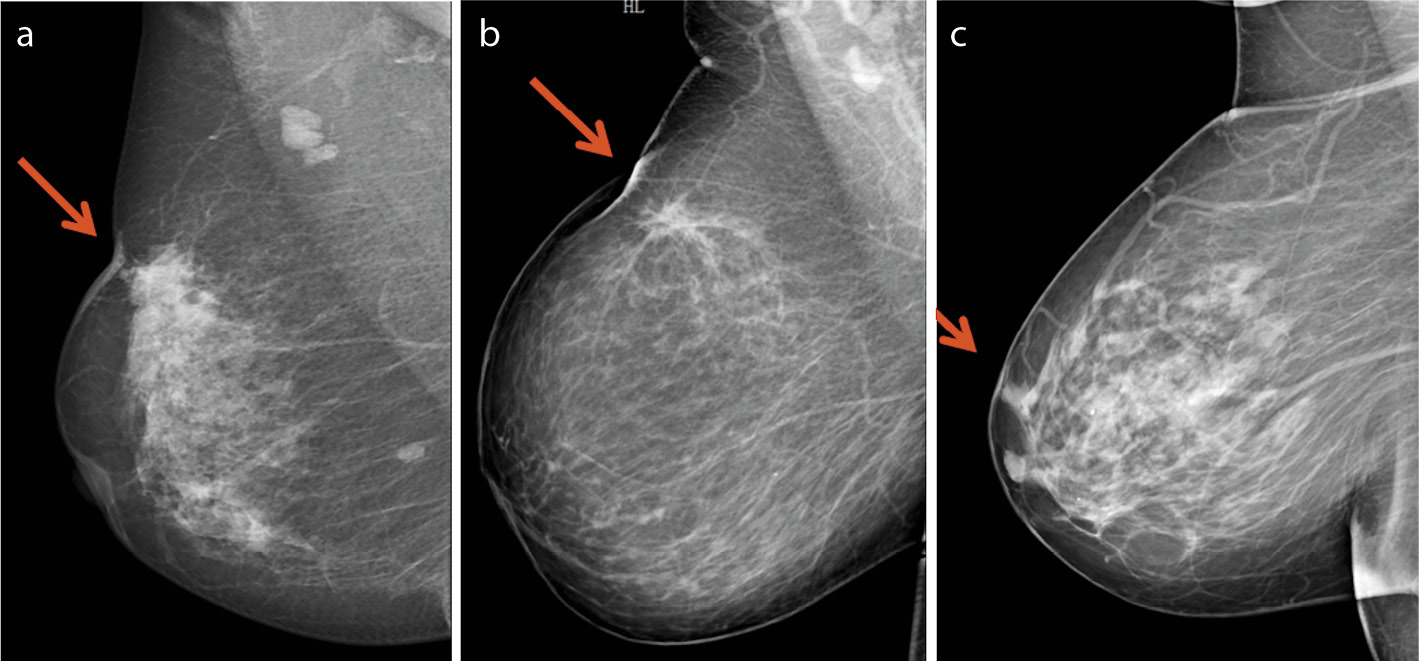

Среди всех методов визуализации в диагностике локального и диффузного отека кожи маммография характеризуется наиболее высокой эффективностью за счет возможности анализа симметричных зон «суммационного» изображения органа. При этом основным признаком отека кожи является ее утолщение (рис. 1). С помощью ультразвукового исследования молочных желез также возможно визуализировать отек кожи за счет утолщения и активного кровоснабжения кожного покрова (рис. 2). Но данный метод субъективен и обладает низкой результативностью в выявлении локального отека кожи. Роль магнитно-резонансной томографии молочных желез в решении этого вопроса незначительна (рис. 3), и поэтому этот вид визуализации не может использоваться для дифференциальной диагностики злокачественной и доброкачественной природы отека (уровень доказательности 1b, уровень рекомендаций A) [4].

Рис. 1. Маммограммы в прямой и косой проекциях. ОИФ РМЖ. Определяются утолщение кожи на всем протяжении, диффузная инфильтрация ткани молочной железы (а), метастатическое поражение аксиллярных лимфоузлов (b).